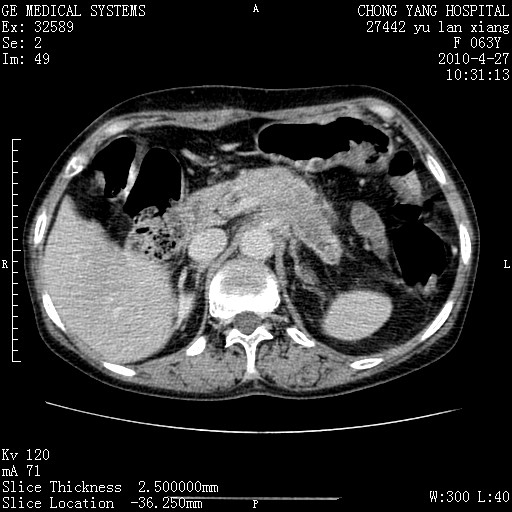

标题: CT26066:F63Y 上腹正中压痛半月,CA199:7400u/ml,MR示胰腺炎伴 [打印本页]

胰腺癌侵犯腹腔动脉干-分支、胃壁、左侧膈肌伴胰周及腹膜后淋巴结转移、胆囊切除术后。

胰腺癌侵犯腹腔动脉干-分支、胃壁、左侧膈肌伴胰周及腹膜后淋巴结转移、胆囊未显影。